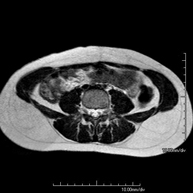

Prova diagnòstica no invasiva que consisteix en l'obtenció d'imatges d'alta definició anatòmica de la pelvis mitjançant l'ús d'un camp electromagnètic i ones de ràdio (amb un emissor i un receptor). No utilitza radiació ionitzant. Es realitza per a l'estudi de patologies d'úter, d'ovari, de trompes i de vagina, ja siguin d'origen tumoral, inflamatori o vascular. També permet valorar les estructures adjacents localitzades a la pelvis i la identificació de les seves alteracions. De vegades és necessari l'ús de contrast intravenós (Gadolini) per caracteritzar les lesions. - RM Pelvis masculina

Prova diagnòstica no invasiva que consisteix en l'obtenció d'imatges d'alta definició anatòmica de la pelvis masculina mitjançant l'ús d'un camp electromagnètic i ones de ràdio (amb un emissor i un receptor). No utilitza radiació ionitzant. No requereix preparació prèvia. En algunes ocasions necessita l'ús de contrast paramagnètic (Gadolini) per caracteritzar les lesions. Aquesta prova permet valorar òrgans com la bufeta urinària, la unió entre els urèters i la bufeta, la pròstata, les vesícules seminals, la uretra i els ossos de la pelvis, entre d'altres. - RM de Fetge